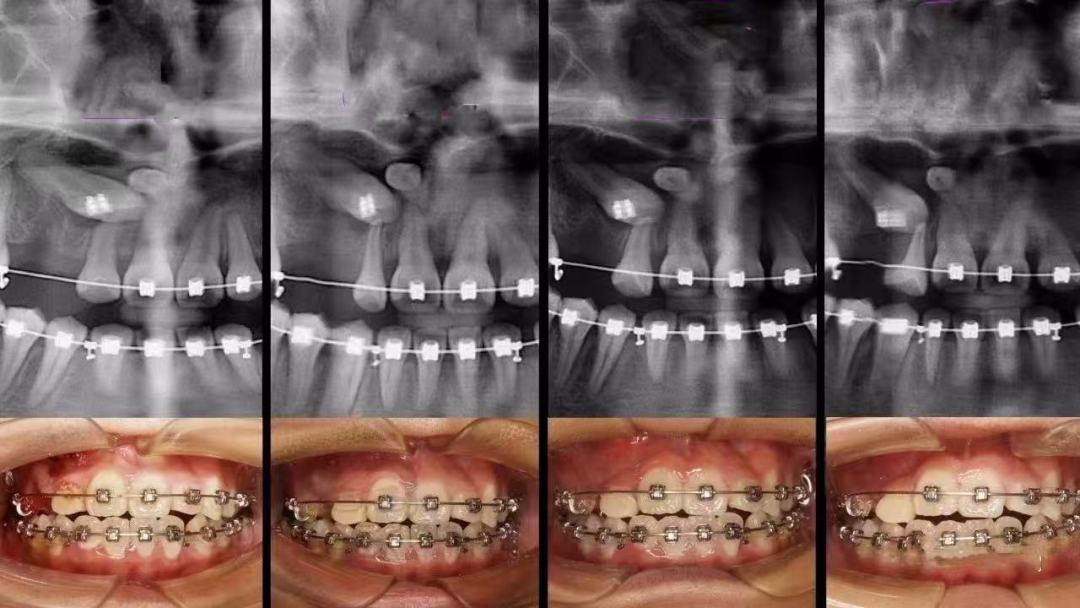

值得庆幸的是,随着多学科联合治疗的开展以及正畸技术的不断发展与完善,更多的上颌前牙埋伏阻生齿得以矫治和保留。通过正畸 - 外科联合牵引助萌复杂埋伏阻生牙的方法,往往能获得良好的效果,帮助患儿健康自信地成长。

如果大家怀疑自己有埋伏牙,一定要及时去正规的口腔医院进行检查。通常情况下,拍个 X 光片就能清楚地看到牙齿的情况了。